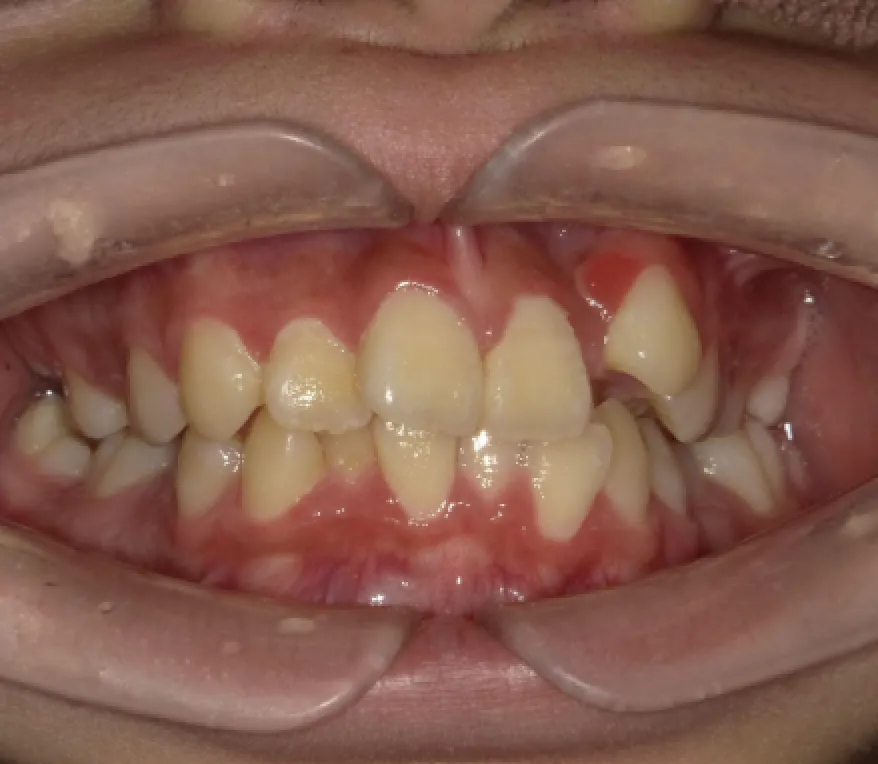

Before

After

性別

年齢

治療費用

治療内容

リスク

副作用

治療期間

女性

10代

902,000円

2年11ヶ月

インビザライン

矯正治療の一般的なリスクといた

しましては、治療中のお痛み・歯

根吸収・歯肉退縮・治療後の後戻

りなどが生じる可能性があります。矯正治療は始めると、元の状態に

戻すのが難しいことがあります。